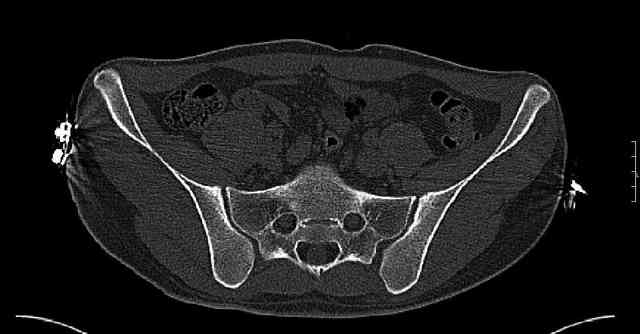

The joint is non-concentric as the head appears to be either "following the caudal segment", or the dome component is displaced from the tethered head... or so it seems... and he's young... so, many fracture surgeons would recommend reduction and fixation.

So we must decide preoperatively which part is the displaced segment?

It's difficult to know from these few selected images which component of the injury (was before and now) should be deemed the "soon to be mobile"

segment. It's my best guess that it is the caudal portion and there exists a healing fracture line somewhere thru the posterior column...one image

suggests it. If true, its early healing/union should be disrupted, and the resultant fragment mobility then allows accurate reduction.

Some more images. Does it help to guess which part of the acetabulum is displaced?

Normal appearing SI joints and a healed posterior column limb... my bet's on caudal segment displacement.